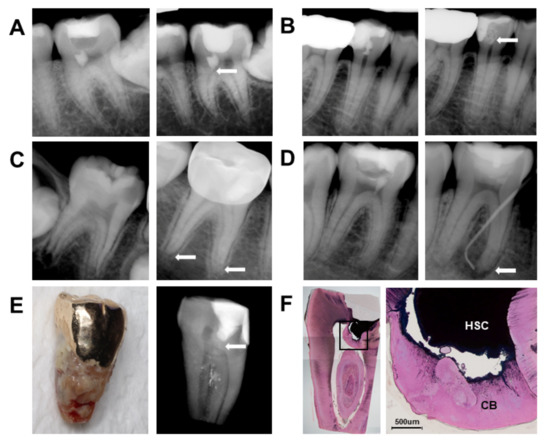

2.5. Histologic Evaluation